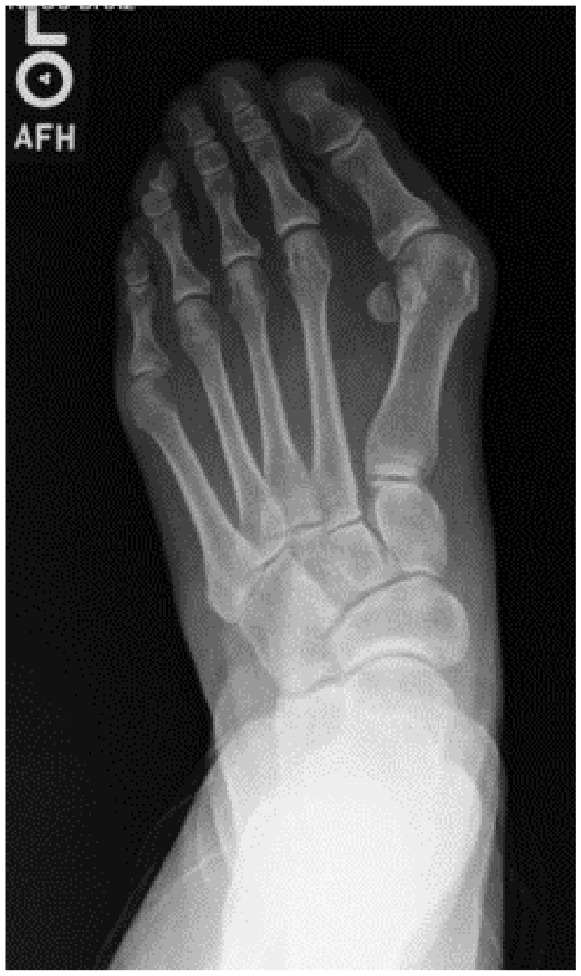

Background: Recent literature highlights the importance of treating hallux valgus (HV) as a 3-dimensional (3D) deformity. Although 3D printing may enhance visualization of the multiplanar aspects of HV, its influence on surgical planning remains unclear. This study assessed changes in surgical plans when surgeons sequentially reviewed 2D radiographs, 3D weightbearing computed tomography (WBCT), and 3D-printed models, hypothesizing that 3D printing would have the greatest impact.

Methods: A single HV case (a 40-year-old woman, intermetatarsal angle [IMA] 21 degrees, HV angle [HVA] 47 degrees) was evaluated by 30 surgeons in a masked, stepwise manner. Surgical plans were recorded at each stage. Surgeons rated the influence of WBCT and 3D printing using a 5-point Likert scale. A follow-up survey examined the effect of these technologies on correction amplitudes.

Abstract Image